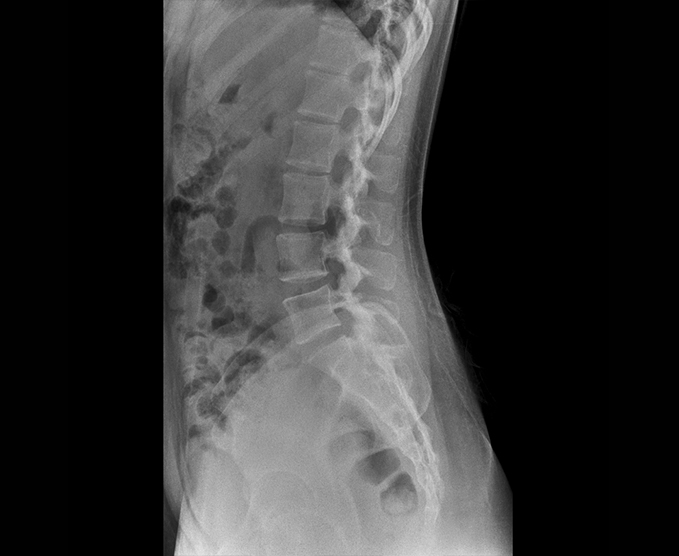

Radiología simple

Una radiografía es una prueba rápida e indolora que genera imágenes de las estructuras internas del cuerpo, en especial de los huesos.

- Rodilla